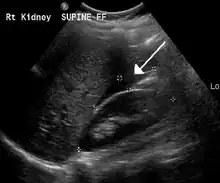

An ultrasound showing a gestational sac with fetal heart in the fallopian tube has a very high specificity of ectopic pregnancy. Transvaginal ultrasonography has a sensitivity of at least 90% for ectopic pregnancy.[4] The diagnostic ultrasonographic finding in ectopic pregnancy is an adnexal mass that moves separately from the ovary. In around 60% of cases, it is an inhomogeneous or a noncystic adnexal mass sometimes known as the "blob sign". It is generally spherical, but a more tubular appearance may be seen in case of hematosalpinx. This sign has been estimated to have a sensitivity of 84% and specificity of 99% in diagnosing ectopic pregnancy.[4] In the study estimating these values, the blob sign had a positive predictive value of 96% and a negative predictive value of 95%.[4] The visualization of an empty extrauterine gestational sac is sometimes known as the "bagel sign", and is present in around 20% of cases.[4] In another 20% of cases, there is visualization of a gestational sac containing a yolk sac or an embryo.[4] Ectopic pregnancies where there is visualization of cardiac activity are sometimes termed "viable ectopic".[4]

Transvaginal ultrasonography of an ectopic pregnancy, showing the field of view in the following image.

A "blob sign", which consists of the ectopic pregnancy. The ovary is distinguished from it by having follicles, whereof one is visible in the field. This patient had an intrauterine device (IUD) with progestogen, whose cross-section is visible in the field, leaving an ultrasound shadow distally to it.